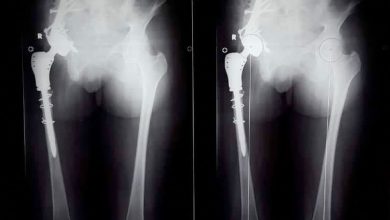

إجراء عملية جراحية معقدة لإزالة ورم من مفصل الحوض بجامعة أسيوط

نجح فريق طبي من قسم جراحة العظام بمستشفى أسيوط الجامعي، في إجراء أول جراحة من نوعها، لاستئصال ورم من عظمة…